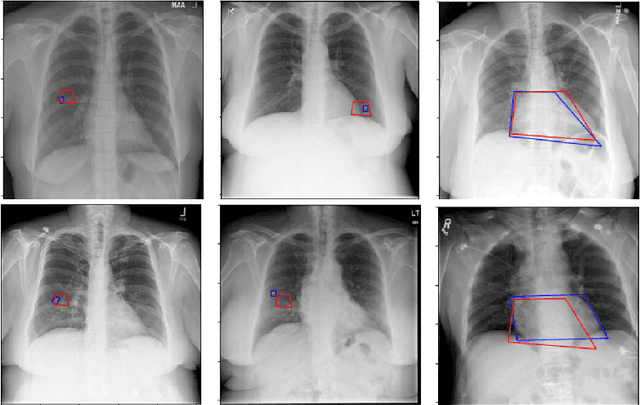

Abstract:Medical image analysis practitioners have embraced big data methodologies. This has created a need for large annotated datasets. The source of big data is typically large image collections and clinical reports recorded for these images. In many cases, however, building algorithms aimed at segmentation and detection of disease requires a training dataset with markings of the areas of interest on the image that match with the described anomalies. This process of annotation is expensive and needs the involvement of clinicians. In this work we propose two separate deep neural network architectures for automatic marking of a region of interest (ROI) on the image best representing a finding location, given a textual report or a set of keywords. One architecture consists of LSTM and CNN components and is trained end to end with images, matching text, and markings of ROIs for those images. The output layer estimates the coordinates of the vertices of a polygonal region. The second architecture uses a network pre-trained on a large dataset of the same image types for learning feature representations of the findings of interest. We show that for a variety of findings from chest X-ray images, both proposed architectures learn to estimate the ROI, as validated by clinical annotations. There is a clear advantage obtained from the architecture with pre-trained imaging network. The centroids of the ROIs marked by this network were on average at a distance equivalent to 5.1% of the image width from the centroids of the ground truth ROIs.